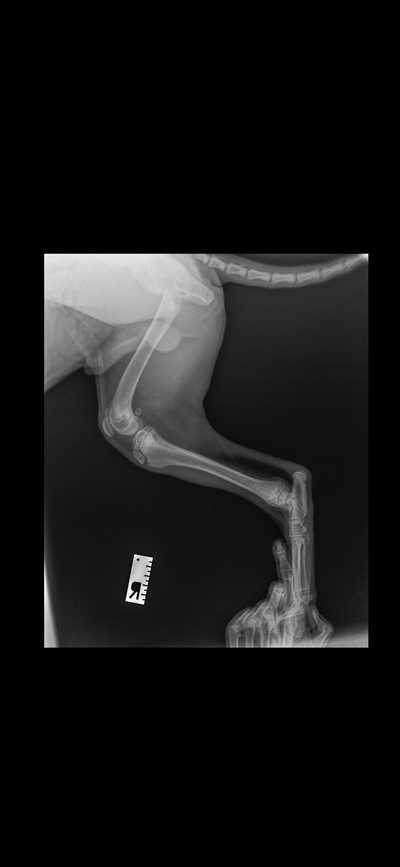

Тоже недавно делали рентген нашей булки)

Иллюстрация к комментарию

Когда бесилась неудачно спрыгнула, пару дней прихрамывала, серьёзного ничего нет, булка счастлива